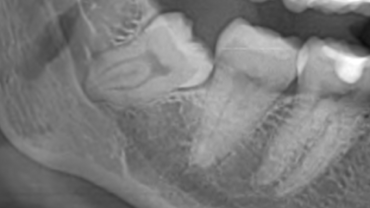

[Immagine di un dente del giudizio in contiguità con il canale mandibolare] La lesione del… Leggi

Ortodonzia estrattiva: il dente del giudizio viene allontanato con tecnica ortodontica dal nervo alveolare inferiore